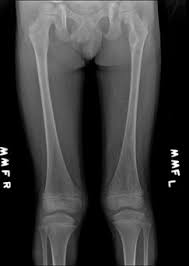

An enchondroma is a benign cartilage tumour found inside bones. Hemimegalencephaly is a rare congenital disorder of cortical formation with hamartomatous overgrowth of all or part of a cerebral hemisphere. Albright hereditary osteodystrophy pseudohypoparathyroidism a disorder involving the inability to respond to parathyroid hormone affecting bone growth and height Fibrous dysplasiaMcCune Albright syndrome a disorder that affects bones skin pigment and the endocrine system.

Typically enchondroma is discovered on an X-ray scan. Oral Surgery Oral Medicine Oral Pathology and Oral Radiology Vol. It may predominantly affect the medullary portion andor cortex of bone. Each chapter in GeneReviews is written by one or more experts on the specific condition or disease. And The result of the test will directly impact the treatment being delivered to the member. OMIM174800 is a rare disorder characterized by skeletal lesions skin hyperpigmentation and hyper-functioning endocrinopathies 1 2It arises from post-zygotic gain-of-function mutations in the GNAS gene which encodes the α-subunit of the G s signalling protein These mutations disrupt the intrinsic GTPase. Cafè-au-lait skin pigmentations and endocrine dysfunction such as precocious puberty diabetes mellitus goiter and breast fibroadenomatosis 7 Radiographic features Typically seen as a well-circumscribed intramuscular mass. Oral Surgery Oral Medicine Oral Pathology Oral Radiology is required for all clinicians involved in the diagnosis and treatment of oral and maxillofacial disease. It is the only major dental journal that.